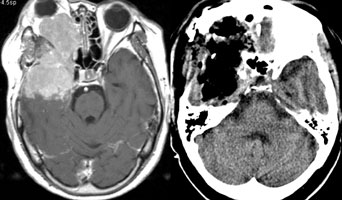

<¸ð¾ß¸ð¾ßº´(¼Ò¾ÆÁßdz)>

¿ìÃø

³»°æµ¿¸ÆÀÇ Æó»ö¼Ò°ß°ú °æµ¿¸ÆºÎÀ§ÀÇ

ÀÌ»óÇ÷°ü¸Á ¼Ò°ßÀÌ º¸À̰í ÀÖ´Ù. |